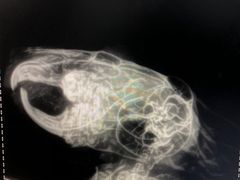

• 瑞派·关忠动物医院·异宠专科·犬猫肿瘤·皮肤专科(望京店)

• -瑞派·关忠动物医院·异宠专科·犬猫肿瘤·皮肤专科(望京店)

染染子 | 22-07-16